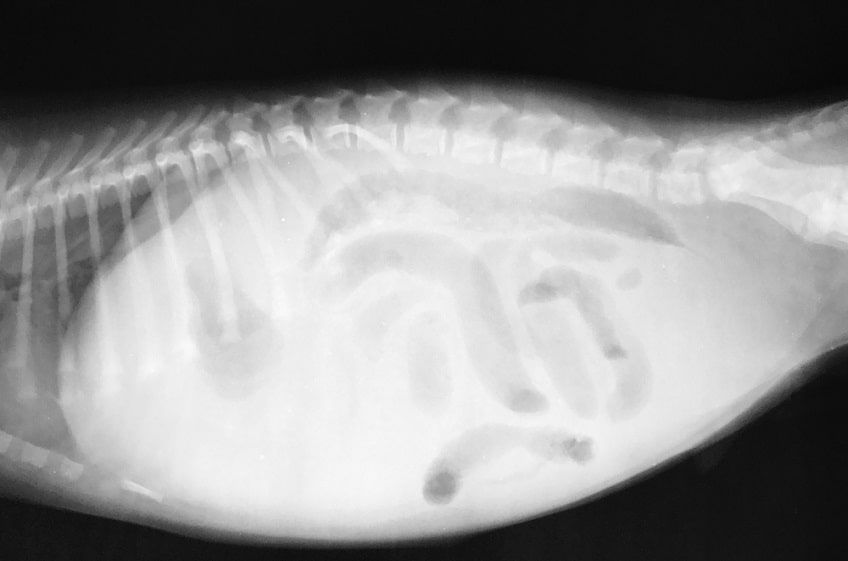

Głównym objawem wodobrzusza u psa jest symetryczne powiększenie powłok brzusznych, które rozdymają się pod wpływem płynu, który z różnych przyczyn gromadzi się w jamie otrzewnej. Płyn ten zaczyna wywierać ucisk na narządy jamy brzusznej, w tym przeponę, powodując u psa dyskomfort, ból i trudności z oddychaniem. Wodobrzusze może także utrudniać psu poruszanie się, a nawet uniemożliwiać jedzenie i picie.

Do potwierdzenia wodobrzusza u psa niezbędne będzie przeprowadzenie badań obrazowych. Szczególnie przydatne jest badanie USG, które pozwoli na ocenę narządów wewnętrznych psa i wykrycie ewentualnych guzów nowotworowych. Po stwierdzeniu wodobrzusza u psa lekarz weterynarii może zadecydować o przeprowadzeniu punkcji i odsączeniu płynu z jamy brzusznej. Analiza składu i badanie cytologiczne zebranego płynu puchlinowego pomoże w zdiagnozowaniu przyczyny problemu. Ponadto psu należy wykonać badanie krwi i EKG.